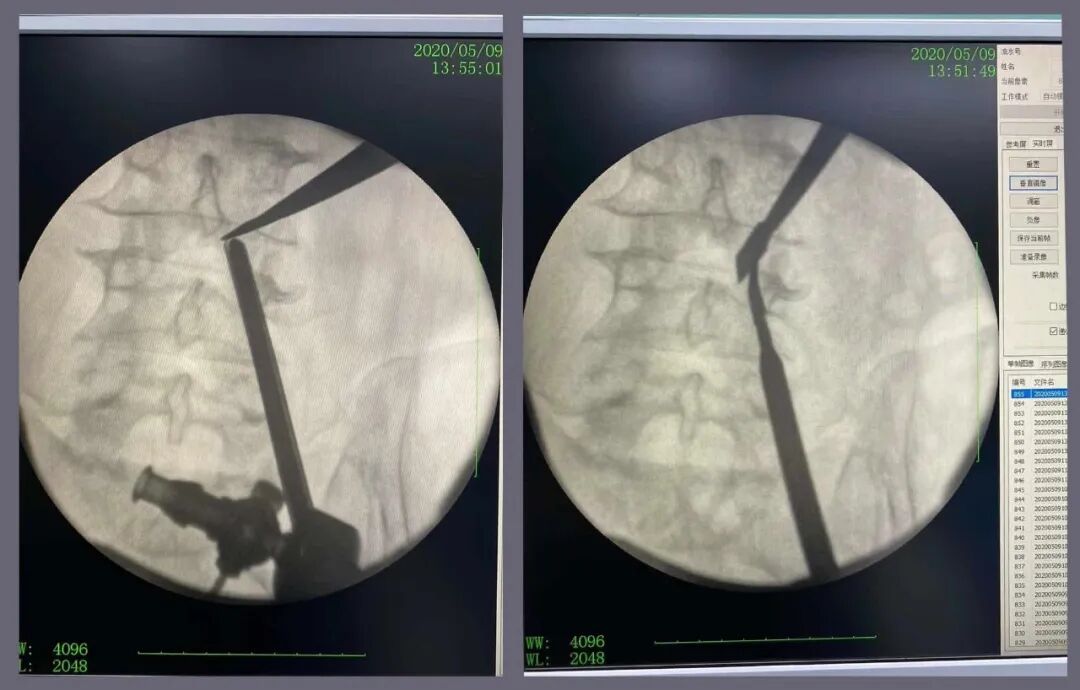

▲2020年5月9日,一例腰3/4严重椎管狭窄病例,采用单边双通道UBE技术来完成椎间盘减压。

▲UBE术中影像

▲UBE手术 穿刺定位